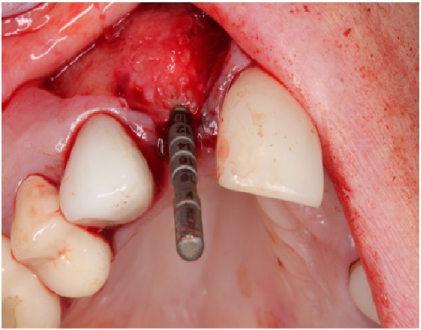

Using bilateral papillae sparing releasing incisions at surgical sites, the Cytoplast® membranes and tacks were removed and the implant sites were prepared showing excellent bone regeneration (Figures 20, Figure 21, and Figure 22). Standard protocol was used to prepare Straumann® Bone Level Tapered implants (Andover, MA, USA). (Figures 20 and Figure 22). Four months post implant placements with all 3 implants osseointegrated and provisional restorations in place. (Figures 23, Figure 24, and Figure 25).

Figure 20: Implant site preparation for a 3.3 × 10 mm Straumann Bone Level Tapered implant. Depth gauge is in place. Notice the amount bone regeneration. View Figure 20